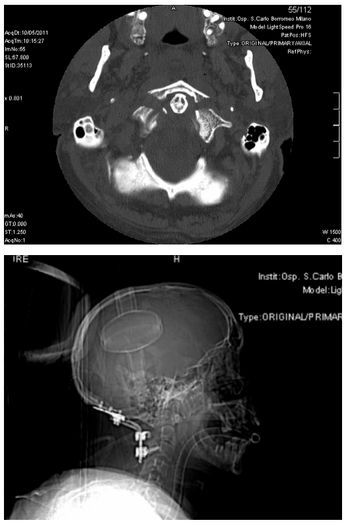

Alcuni casi operati